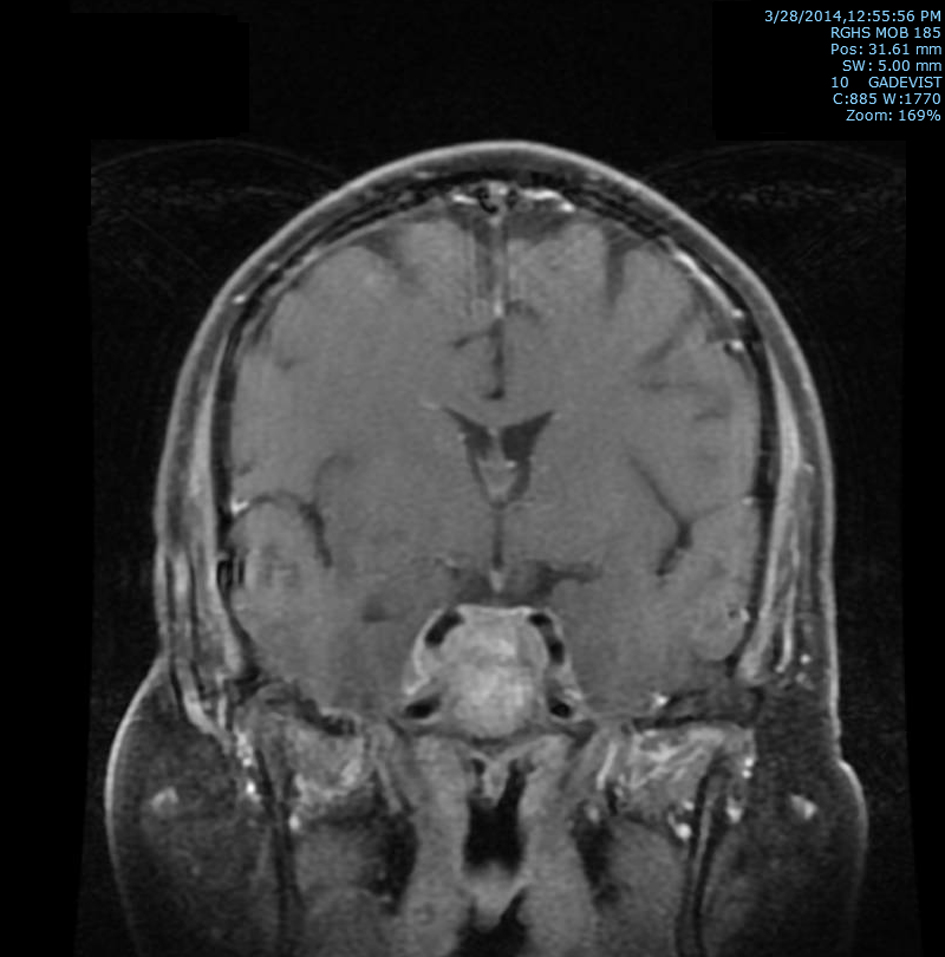

Subsequently, an MRI of the brain showed multiple intraaxial enhancing lesions involving the frontal lobes, cerebellar hemispheres, right occipital lobe in addition to an enhancing, expansile mass in the clivus with soft tissue component in the right cavernous sinus extending anteriorly into the sphenoid sinus (Fig. 1), superiorly into the sella and posteriorly into the pre-pontine cistern. There was encasement of the right internal carotid artery and presence of moderate associated vasogenic edema (Fig. 2). All of these findings were most suggestive of intracranial metastatic disease. Due to the presentation of multiple metastatic sites in the brain, it was not felt necessary to biopsy the cavernous sinus lesion.

![]() Click for large image | Figure 2. T2 post-contrast coronal MRI image of brain showing extension superiorly into the sella and posteriorly into the prepontine cistern with soft tissue prominence of right cavernous sinus with associated encasement of the right internal carotid artery. |